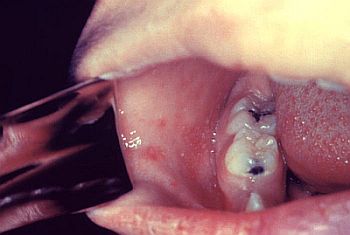

Κηλίδες Koplik Η ιλαρά αρχίζει με μια πρόδρομη αναπνευστική φάση 2-4 ημερών που εμφανίζεται με αίσθημα κακουχίας, βήχα, κόρυζα, επιπεφυκίτιδα με δακρύρροια, ρινικό καταρροή και αυξανόμενο πυρετό (με θερμοκρασίες έως 40,6°C). Στο στάδιο αυτό της νόσου, κατά το οποίο το εξάνθημα ακόμη δεν έχει εμφανιστεί, είναι πιθανόν να δημιουργηθεί σύγχυση με τη γρίπη. Λίγο πριν την έναρξη του εξανθήματος εμφανίζονται οι κηλίδες Koplik ως κυανόλευκες κηλίδες 1-2 mm επί έντονα ερυθρής βάσης που εντοπίζονται χαρακτηριστικά στον στοματικό βλεννογόνο, παραπλεύρως των δεύτερων γομφίων και υποχωρούν μετά την έναρξη του εξανθήματος και σύντομα εξαφανίζονται (ουσιαστικά πρόκειται για ανοσοαπαντήσεις κατά του ιού στα ενδοθηλιακά κύτταρα των τριχοειδών).